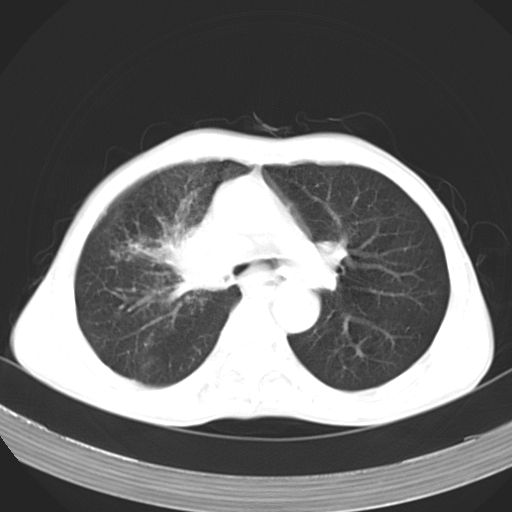

以下是引用苯小孩在2007-5-24 12:47:00的发言:[br]右侧肺门处不均匀密度软组织块影,远端肺组织见斑片模糊影,纵隔内淋巴结明显肿大,边界不清.<纵隔窗第12层面支气管内似见软组织结节>[br]考虑:1、右侧中央性肺癌并阻塞性肺炎并纵隔淋巴结转移可能性大.建议强化或纤支镜进一步检查.[br]2、隆突下淋巴结肿大/食道病变?请做鉴别检查.

以下是引用zhangzhongshou在2007-5-24 12:55:00的发言:[br]1、右肺中叶中心型肺癌并右肺门、隆突下、纵隔淋巴结转移。右肺中叶阻塞性肺炎。

以下是引用jw-830在2007-5-24 15:24:00的发言:[br][br] [br] 考虑右肺中央型肺癌并阻塞性炎症,右肺门及纵隔淋巴结转移。 [br] [br][br]